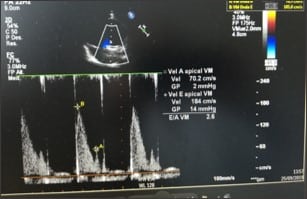

- E/E’ > 20, relación E/A >2.

- Patrón restrictivo.

- Volumen aurícula izquierda elevado desde la cirugía.